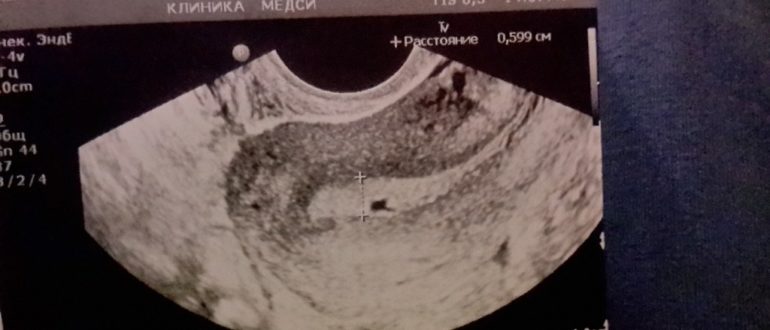

УЗИ непонятный результат

Почему на УЗИ один врач видит то, чего не видит другой? Ультразвуковое исследование помогает безболезненно проверить почти все органы. Но при проведении УЗИ врачи иногда ошибаются и пугают сомнительными диагнозами….